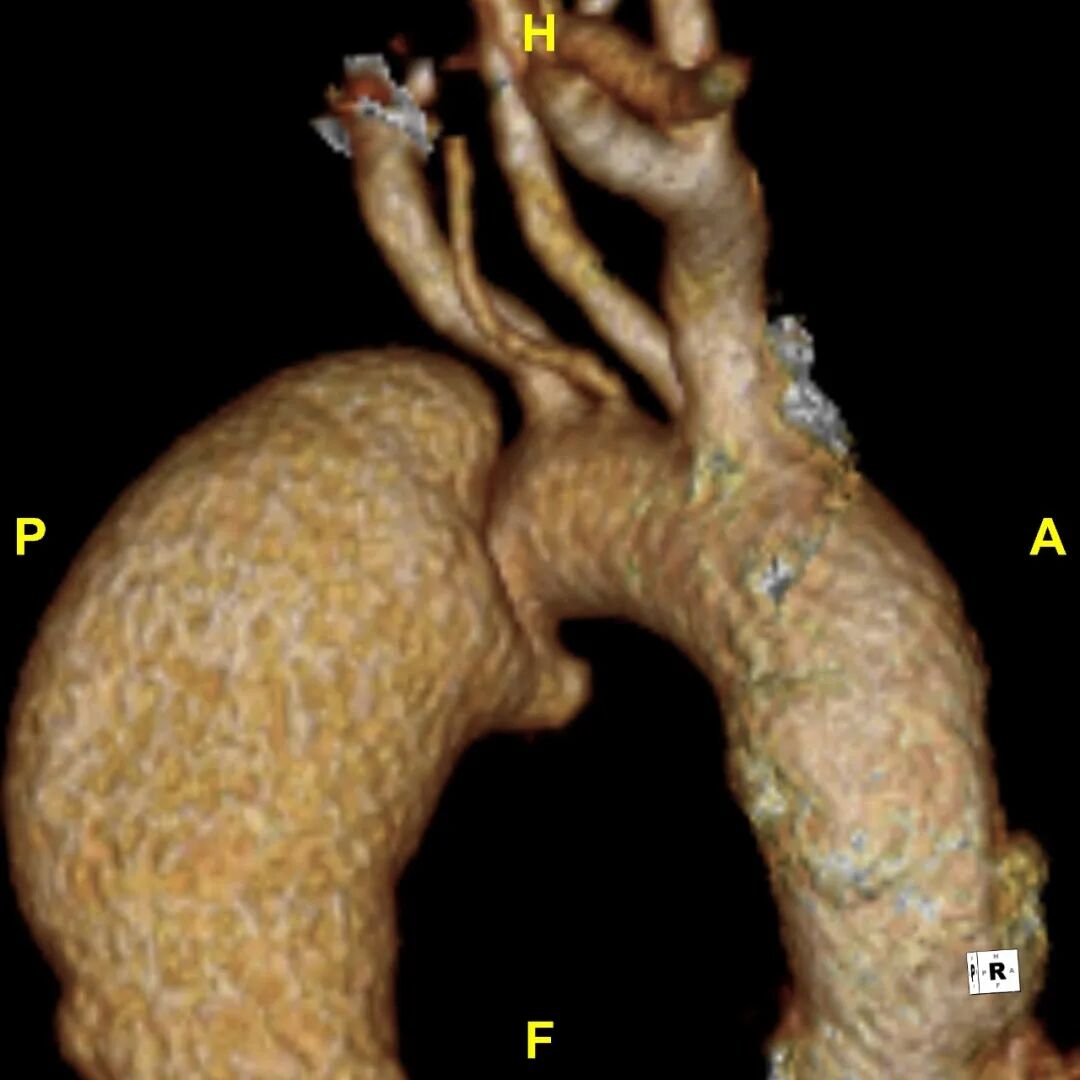

病例2

患者 10月前因“梗阻性黄疸、胆总管结石”检查发现主动脉夹层B型,否认腹痛、腰背痛,追问病史,2019年曾出现胸痛,行冠脉造影未见异常,当时血压170mmHg。诊断为:B型主动脉夹层累及到LSA后缘,左侧椎动脉发自于主动脉弓上的变异解剖形态

3.术前VS术后(3D影像)

gore医疗怎么样「胸有乾坤」释半功倍 得心应手——GORE®TAG® 可主动调控胸主动脉覆膜支架治疗B型主动脉夹层病例分享 复旦大学附属中山医院_https://www.jmylbn.com_新闻资讯_第16张

gore医疗怎么样「胸有乾坤」释半功倍 得心应手——GORE®TAG® 可主动调控胸主动脉覆膜支架治疗B型主动脉夹层病例分享 复旦大学附属中山医院_https://www.jmylbn.com_新闻资讯_第17张